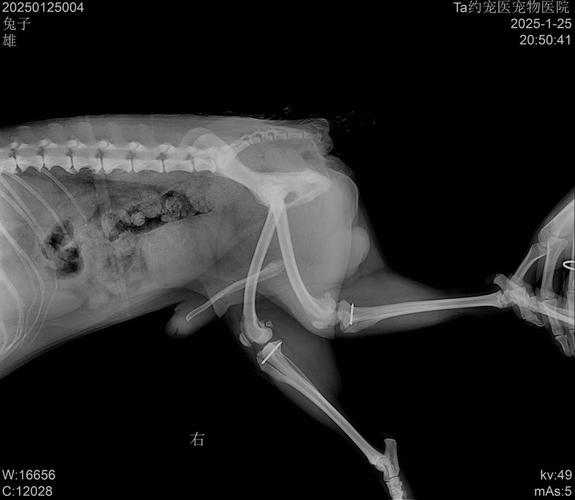

图中可见髌骨脱离滑车沟,关节结构异常)症状表现:运动时明显跛行(如跑动时三腿跳跃,但短距离快速奔跑可能因惯性掩盖症状)。长期脱位导致关节粘连、肌肉萎缩,最终可能引发疼痛(但部分狗狗因耐受性强,早期疼痛不明显)。风险:若不治疗,可能继发关节炎、关节强直,甚至影响对侧肢体健康。

狗狗的骨头发出响声并不一定意味着髌骨脱位。髌骨脱位是一种常见的犬类骨科问题,特别是在小型犬种中。髌骨脱位通常表现为狗狗在行走时突然抬起一条后腿,或者出现跛行、跳跃步态等症状。髌骨脱位可以通过触诊和X光检查来确诊。